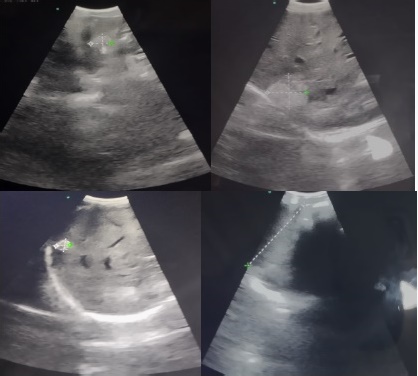

Paciente quien presenta mejoría clínica expresada en desaparición de masa abdominal palpable asi como síntomas dispépticos previamente descritos, se realiza rastreo ecográfico evidenciando disminución significativa de tamaño de las lesiones (Figura 4).